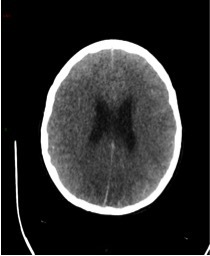

Un scanner cérébral sans injection est réalisé. Les reformations axiales vous sont présentées.

Question 10 : Ce scanner présente :

Les espaces sous sous-arachnoidiens ne sont plus visibles. Ne pas confondre la substance grise qui arrive au contact des os du crâne, avec une hyperdensité spontanée méningée.

Le volume des ventricules paraît faussement augmenté du fait de l’effacement diffus des sillons corticaux.

Qui traduit une augmentation du volume cérébral.

Aucun des deux hémisphères cérébraux ne passe sous la faux du cerveau. L’augmentation du volume cérébral est diffuse.

Effacement diffus des sillons corticaux avec début de dédifférenciation des de la substance blanche - substance grise notamment des noyaux centraux. Cela traduit un œdème cérébral diffus secondaire à un bas débit cérébral.